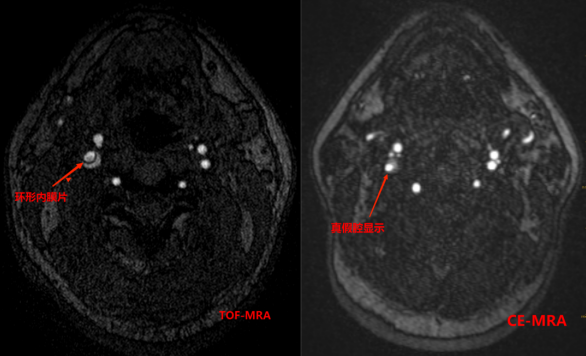

2招丨鉴别烟雾病起因

4a3f949703afaff49bceeb50c8e42009.png6f8e0e6e18d899bde5dea1f66560ec8b.png

以上4图发现右侧颈内动脉和左侧颈内动脉末端,大脑中动脉M1M2段多发斑块形成并严重狭窄,颅内多发小血管生成,大脑后动脉代偿性增粗,并部分大脑前动脉交通,考虑为血管内斑块引起的烟雾综合征。